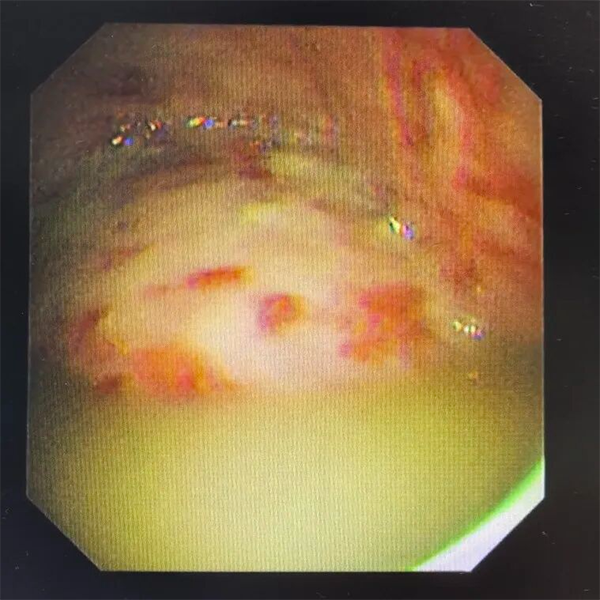

(因带管时间过长并发脓胸、胸腔感染,胸腔镜下见脓液与坏死组织)

面对病情波动,史广林团队迅速行动,在胸腔镜下细致清除了胸腔内的脓液与坏死组织,为肺复张创造了洁净环境。随着感染得到控制,李老伯的恢复进程明显加快。